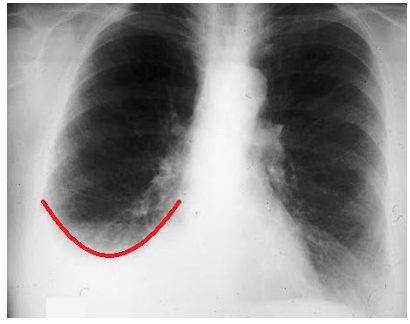

Which imaging study is usually the first study used to identify and quantify the amount of fluid seen with a pleural effusion?

CXR

How much pleural fluid is needed to blunt the costophrenic angle on plain CXR?

~250 mL

Which sign is created as greater amounts of fluid with a pleural effusion opacify the lower thorax?

“Meniscus sign”